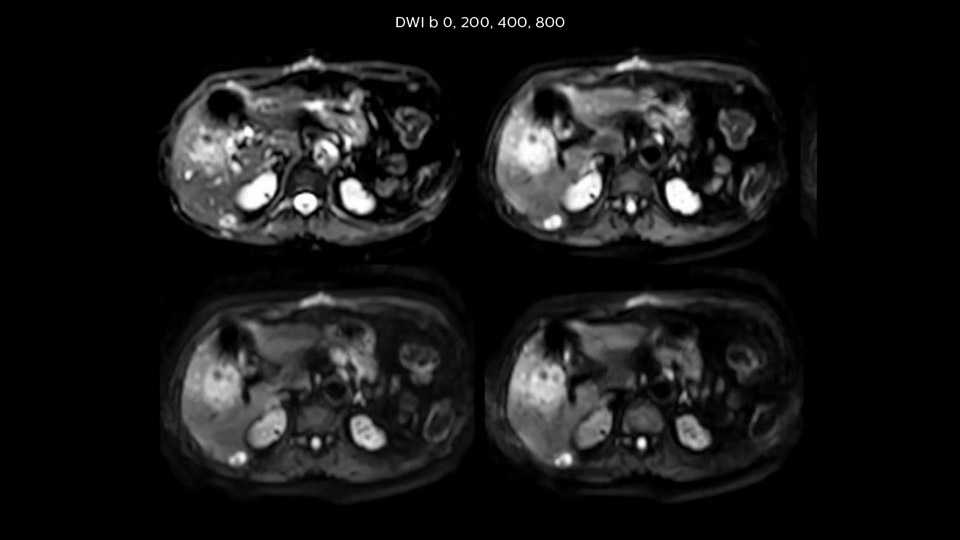

“As we use breathhold imaging for T2-weighted liver scans, we depend on the patient’s ability to cooperate with the exam.

This can present a real challenge when we are looking for small lesions, such as in our oncological patients. However, with MultiVane XD motion correction, we get excellent images. This is important for our surgeons, because they want to know exactly where the lesions are.”

“We acquire one transversal high resolution T2-weighted sequence with 3 mm slice thickness, for example for pancreas or liver lesions. Then we also add a T2 fat suppressed MultiVane XD SPIR sequence. We perform these two routinely in our liver imaging. We use high dS SENSE factors to significantly shorten scan times to 2-4 minutes, which can improve our protocol; it’s a very robust scan.”